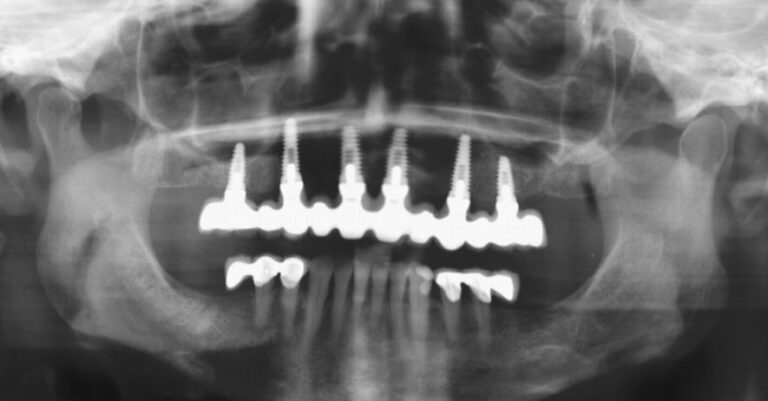

Following improvements to the surfaces of our implants, and utilising experience gained over many years, we can now offer you “FIXED TEETH TODAY”. In most cases, we are able to place a fixed bridge onto the implants immediately after placement. You would therefore arrive at the surgery with loose dentures, and leave with a number of implants placed and a FIXED bridge fitted onto them. This concept reduces the discomfort and healing time following implant placement, and provides immediate satisfaction to our patients. Imagine being able to bite into an apple again for the first time in many years!

The most common cause of partial tooth loss is failing crowns or bridges. The natural roots are then too weak to support a bridge, and have to be extracted. We would usually extract the failing roots, place implants directly into their sockets, and place a fixed bridge immediately afterwards.